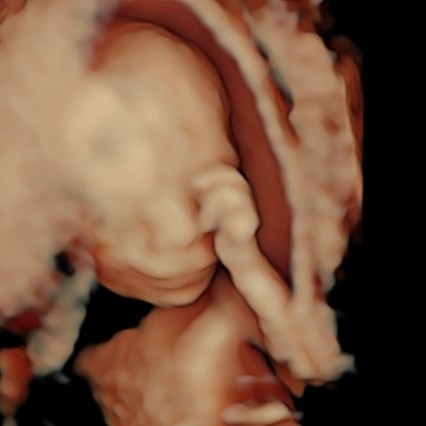

Siamo arrivati al quarto mese. Le incertezze, precauzione e scaramanzie dei mesi precedenti, stanno lasciando il passo a consapevolezza e gioia. L’espressione tipica dei genitori quando guardano il loro “tesoro” a queste settimane è “non pensavo che si vedessero così tante cose e che fosse già così bambino”. Infatti l’impressione ricevuta a queste settimane è di un tesorino alto 14-16 cm e del peso di poco più di 100-180 g, con tutte le sue cosine a loro giusto posto.

A questa epoca è possibile condurre un esame che impropriamente viene definito pre-morfologico, che ci permette di valutare le strutture principali, il tanto da poter affrontare con tranquillità il fondamentale appuntamento con l’ecografia morfologica del V mese.